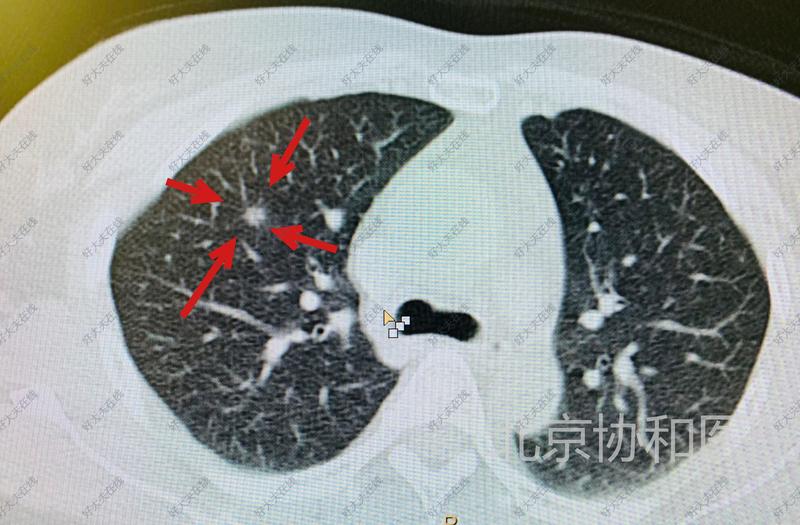

治療前 女性,45歲,體檢發(fā)現(xiàn)右上肺磨玻璃結(jié)節(jié)2年,逐漸長大,胸外科醫(yī)生建議手術(shù)切除,患者本人要求介入消融治療。 治療中 不用開胸,局部麻醉,CT引導(dǎo)下用一根大約鉛筆芯粗的射頻針穿刺肺結(jié)節(jié),針尖產(chǎn)生100度左右的高溫,產(chǎn)熱直徑預(yù)約1.5-2厘米,將結(jié)節(jié)“燒死”,整個操作過程大約30分鐘。術(shù)后1天出院回家。 治療后 治療后1年 術(shù)后每3個月復(fù)查一次肺高分辨CT,1年后改每半年復(fù)查一次。該患者射頻消融治療后1年CT證實(shí),右肺結(jié)節(jié)完全消滅。